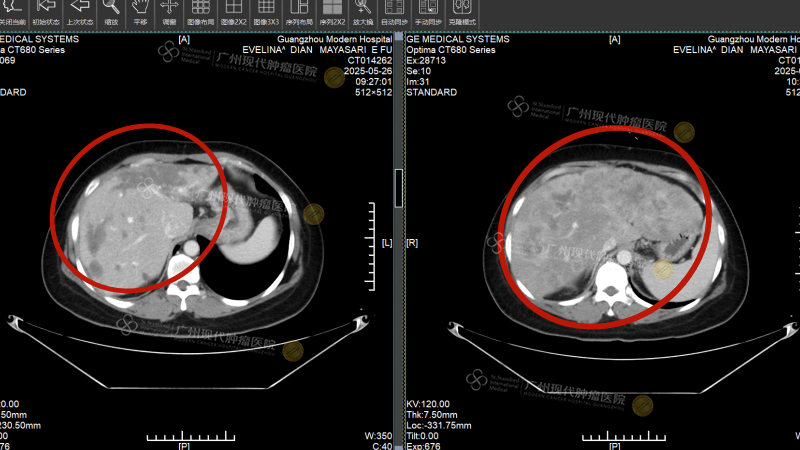

Pada Februari 2025, di tengah teriknya cuaca Kalimantan Tengah, Indonesia, Evelina tersiksa oleh muntah-muntah hebat yang terus berulang hingga tubuhnya kurus kering. Pemeriksaan di rumah sakit setempat menunjukkan adanya benjolan sebesar sekitar 6cm di payudara kirinya, disertai dengan metastasis besar di hati (sekitar 16cm), serta penyebaran ke kelenjar getah bening dan tulang. Hasil biopsi patologi menunjukkan: kanker payudara invasif, ER (-), PR (-), HER-2 (3+), Ki-67 90%.

Sebelum menjalani pengobatan, tumor hati Evelina berukuran sekitar 16cm

Empat minggu kemudian, Intervensi kedua benar-benar membawa keajaiban: Tumor metastasis di hati menyusut dari 16cm menjadi sekitar 2 cm, asites menghilang, dan fungsi hati perlahan kembali normal. Pemeriksaan pencitraan ulang menunjukkan: benjolan di payudara dan lesi di hati menyusut drastis, sebagian bahkan mengalami nekrosis. Saat Evelina mengambil foto liburan di pinggir jalan Guangzhou dan mengirimkannya kepada teman-teman di kampung halamannya, balasan yang ia terima semuanya sama:“Kamu yakin diagnosisnya tidak salah? Ini tidak terlihat seperti pasien kanker!”

Sebelum pengobatan, tumor payudara berukuran 2cm; setelah pengobatan, tumor menghilang

Sebelum pengobatan, tumor hati berukuran sekitar 16cm; setelah pengobatan, tumornya telah kehilangan aktivitas